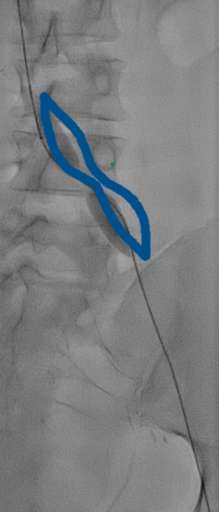

בתמונה 3 ו- 4:

- בכחול מסומן בלון מנופח בלחץ גבוה לפתיחת ההיצרות, ישנה נקודה בווריד עם היצרות קריטית שהיה קשה לפתוח באמצעות הבלון.

- בירוק מסומן תומכן (סטנט) שנפרס אך לא נפתח באופן אופטימלי לאור ההיצרות הקשה.